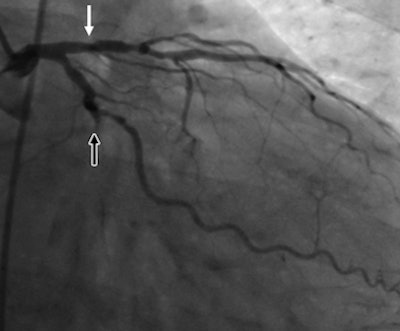

| A 51-year-old man with history of diabetes mellitus presented with typical angina. Above, curved multiplanar reformatted cardiac CT angiographic image read before perfusion shows prominent motion artifact in right coronary artery (arrows) that persisted through all cardiac phases. Below, thick short-axis CT perfusion image at midventricular level shows perfusion defect (arrows) during stress CT perfusion in the inferior and inferolateral segments that is partially reversible during rest CT perfusion. Bottom, reference-standard invasive angiogram findings confirm the presence of severely stenotic lesion in right coronary artery (arrow) that was seen at postperfusion cardiac CTA image reading. Images republished with permission of the Radiological Society of North America. |